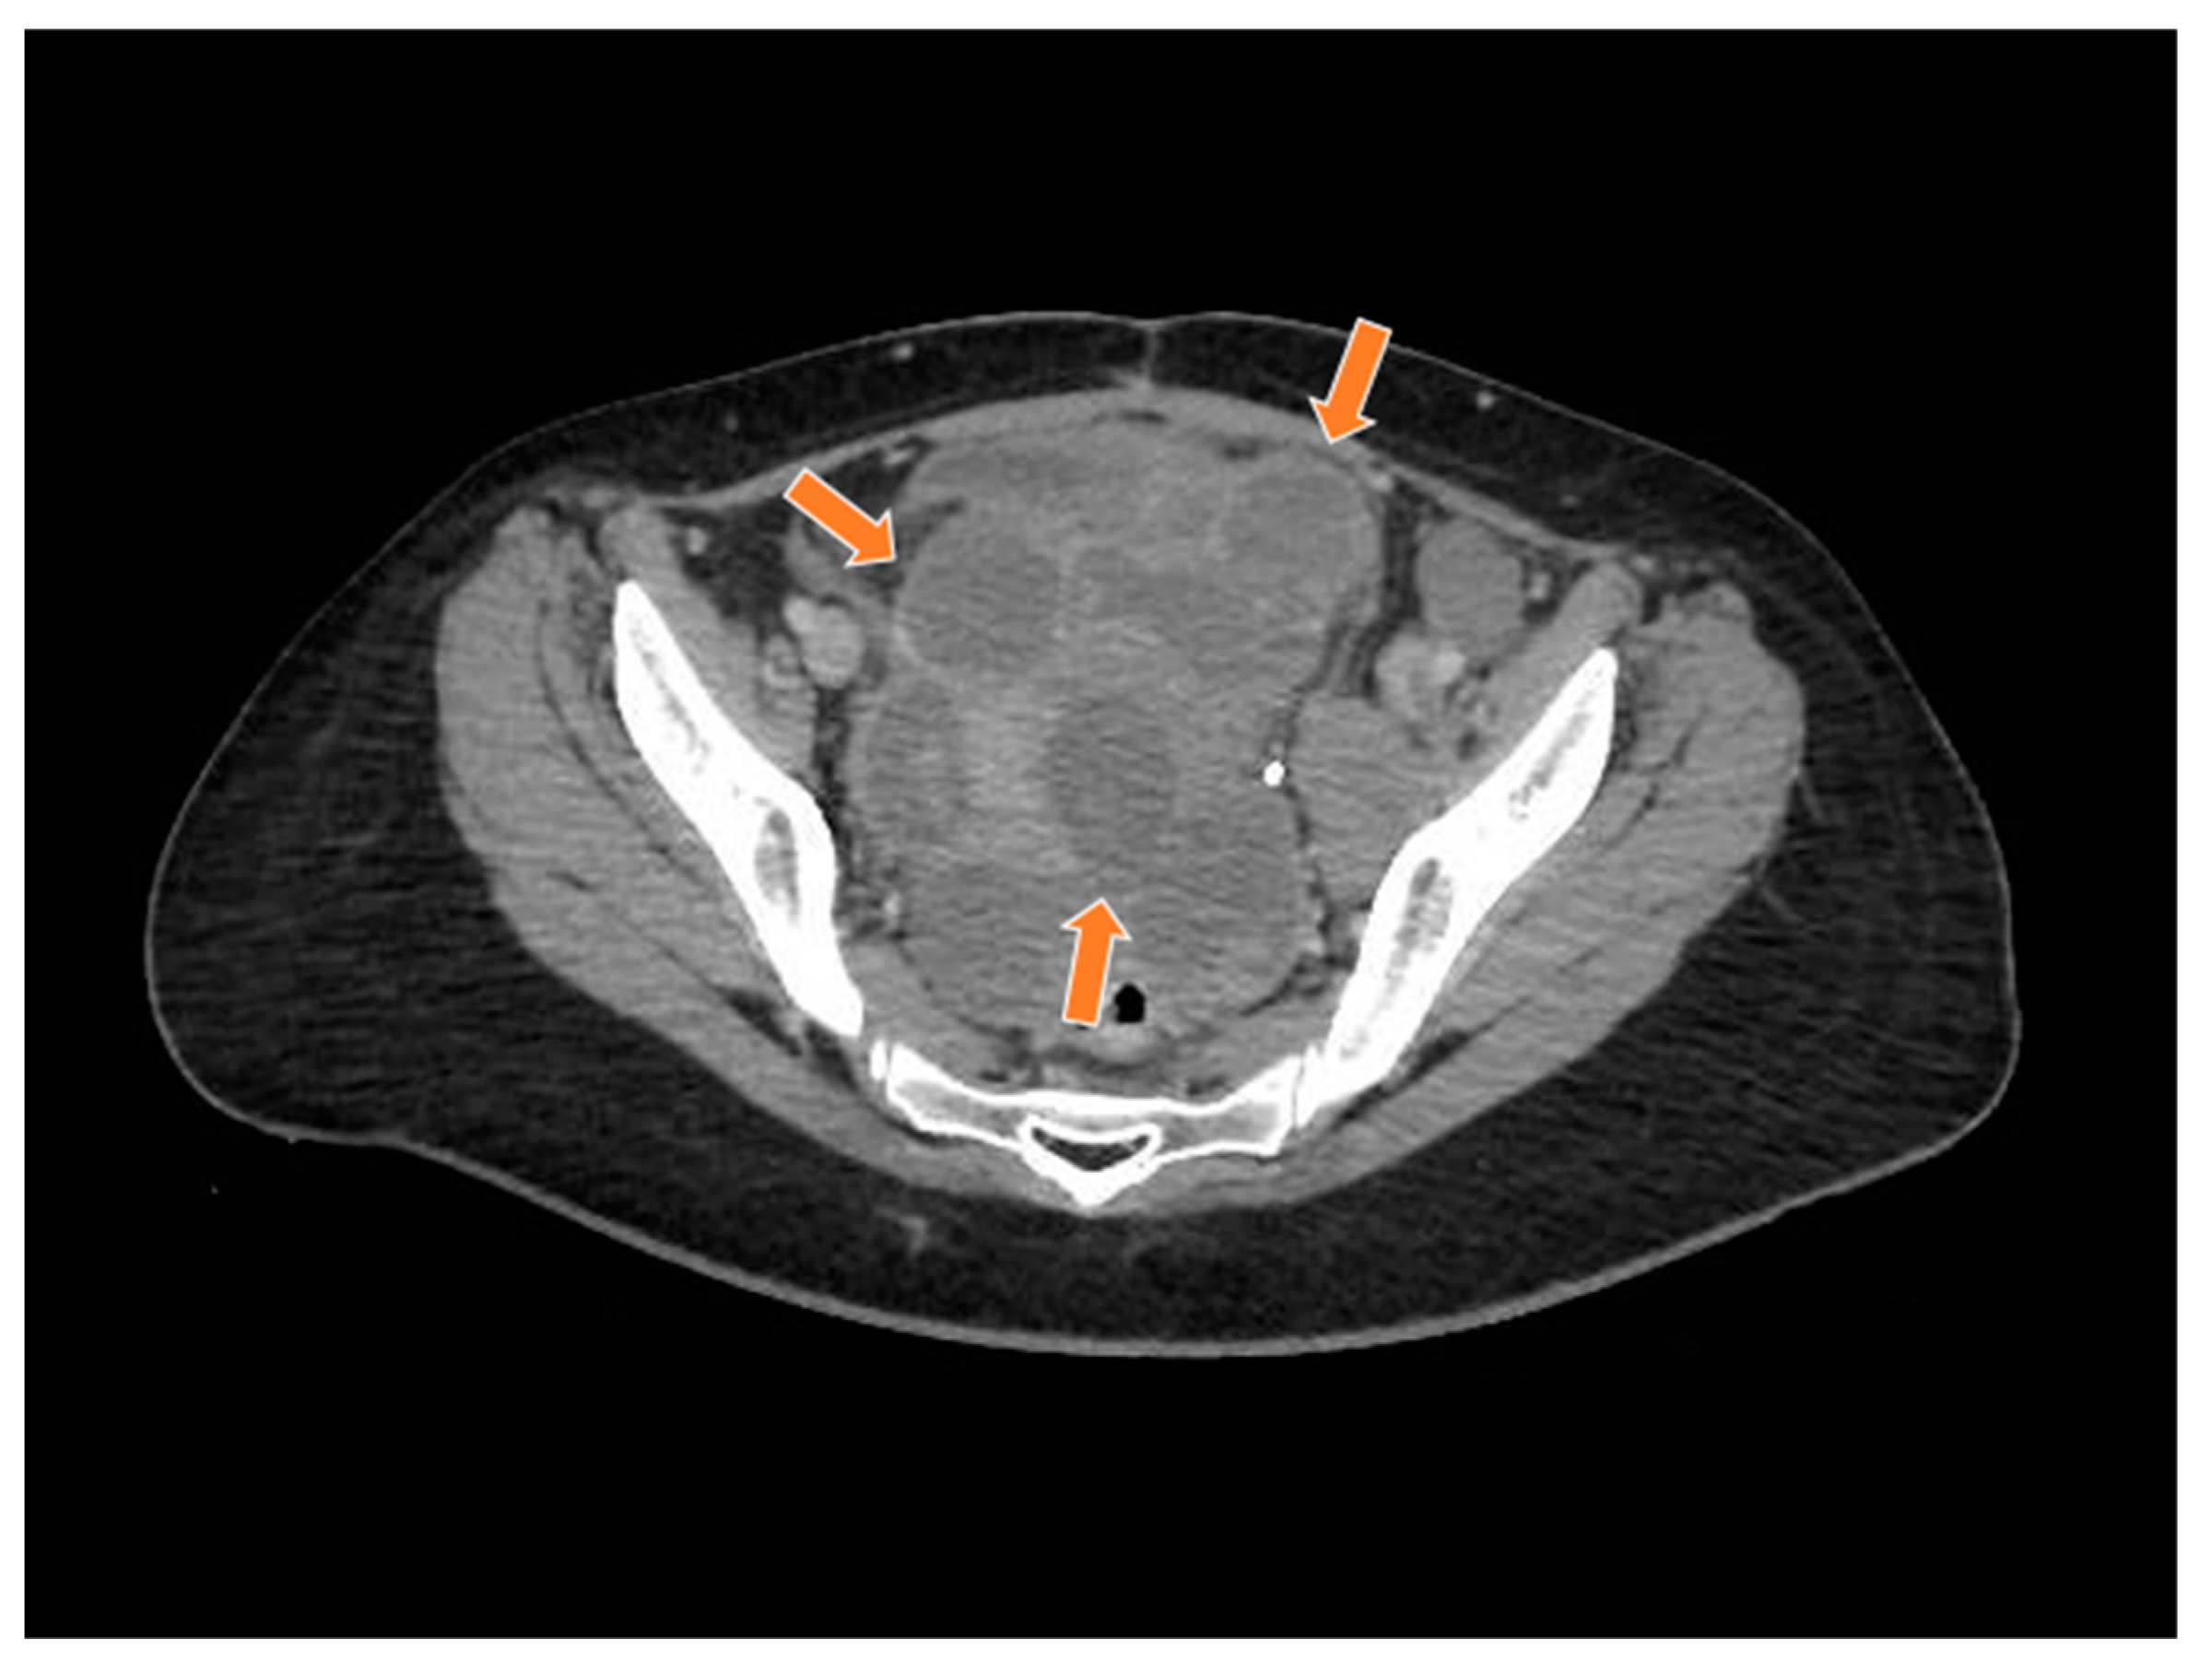

Figure 8.

The computed tomography study in the portal phase showing a heterogeneous lesion in the pelvic region with cystic areas in between (orange arrows).